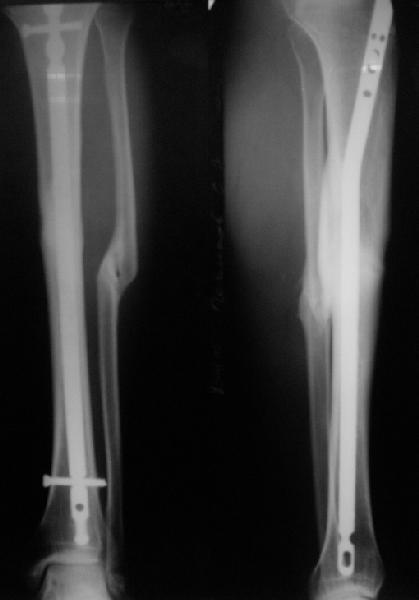

Вот пример, тоже открытый перелом, первичный дефект, пробыл в аппарате 5 мес. Титановый гвоздь,  сразу динамический, без покрытия. Больше не делали ничего.

Имя     : get_image2.jpg

Тип     : image/jpg

Размер  : 19770 байтов

Описание: отсутствует

Url     : http://weborto.net:8080/pipermail/ortho/attachments/20111023/02514467/attachment-0004.jpg